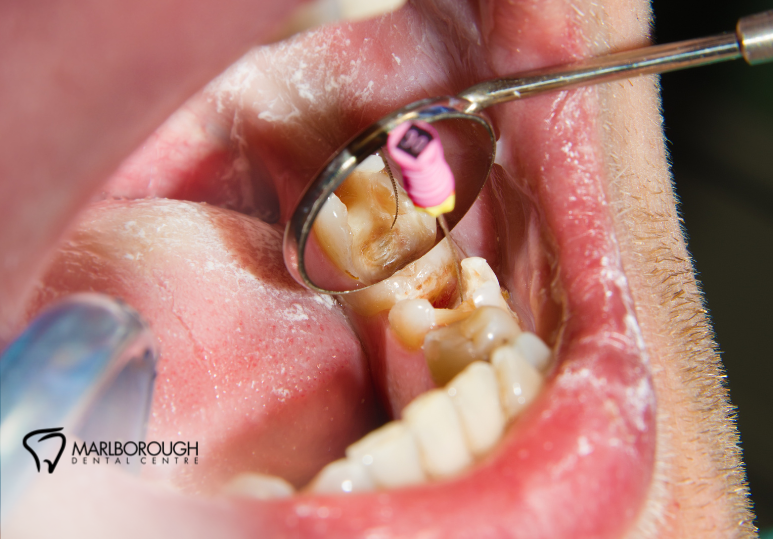

3. Cleaning & Sealing:

We make a small opening in the tooth to access the pulp chamber and root canals. Using specialized tools, we remove the infected pulp, disinfect the canal, and shape it for filling. The space is then filled with a biocompatible material and sealed to protect against future infection.